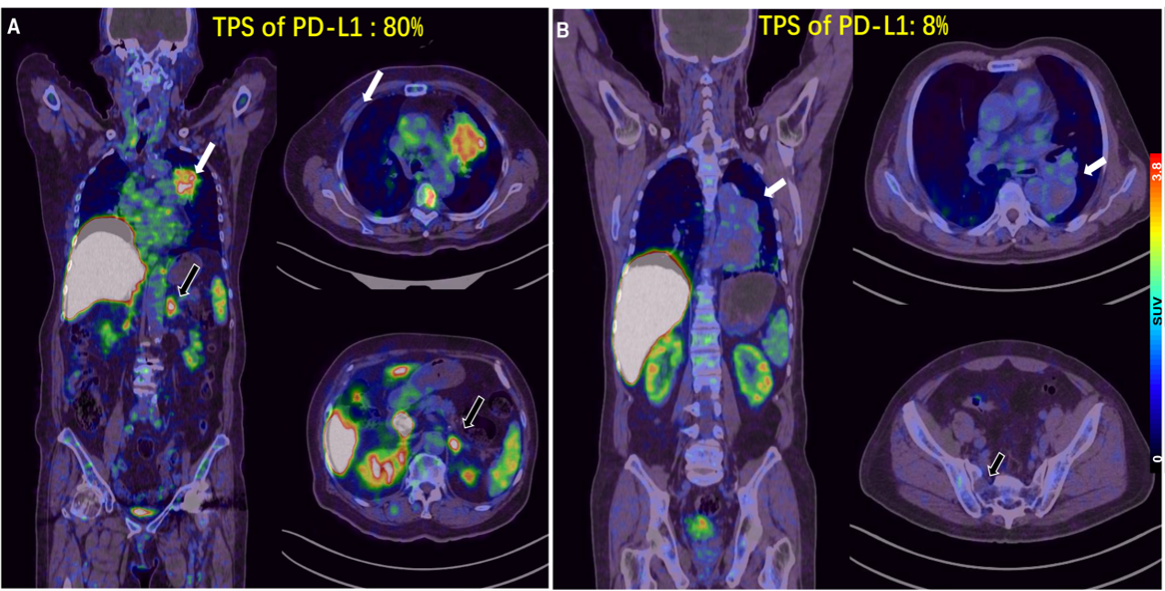

5.目前预测PD-1/PD-L1单抗疗效较为成熟的生物标志物主要是PD-L1表达。北京大学肿瘤医院核医学科和胸部肿瘤内一科合作,研制Ga-68标记的PD-L1靶向低分子量多肽(LMW)探针,首次用于进展期肺癌的临床转化研究展示了在可行的时间窗内用PET显像的方式对患者进行PD-L1表达水平检测的可行性和研究潜力。相关成果以First-in-human evaluation of a PD-L1-binding peptide radiotracer in non-small cell lung cancer patients with PET为题,于 2021年8 月发表在Journal of Nuclear Medicine杂志上。

图5: 68Ga-LMW在不同PD-L1表达水平肿瘤中的PET分析

5. Xin Zhou†, Jinquan Jiang†, Xue Yang†, Teli Liu, Jin Ding, Sridhar Nimmagadda, Martin G Pomper, Hua Zhu*, Jun Zhao*, Zhi Yang*, Nan Li*. First-in-human evaluation of a PD-L1-binding peptide radiotracer in non-small cell lung cancer patients with PET. Journal of Nuclear Medicine, 2021, DOI: 10.2967/jnumed.121.262045.